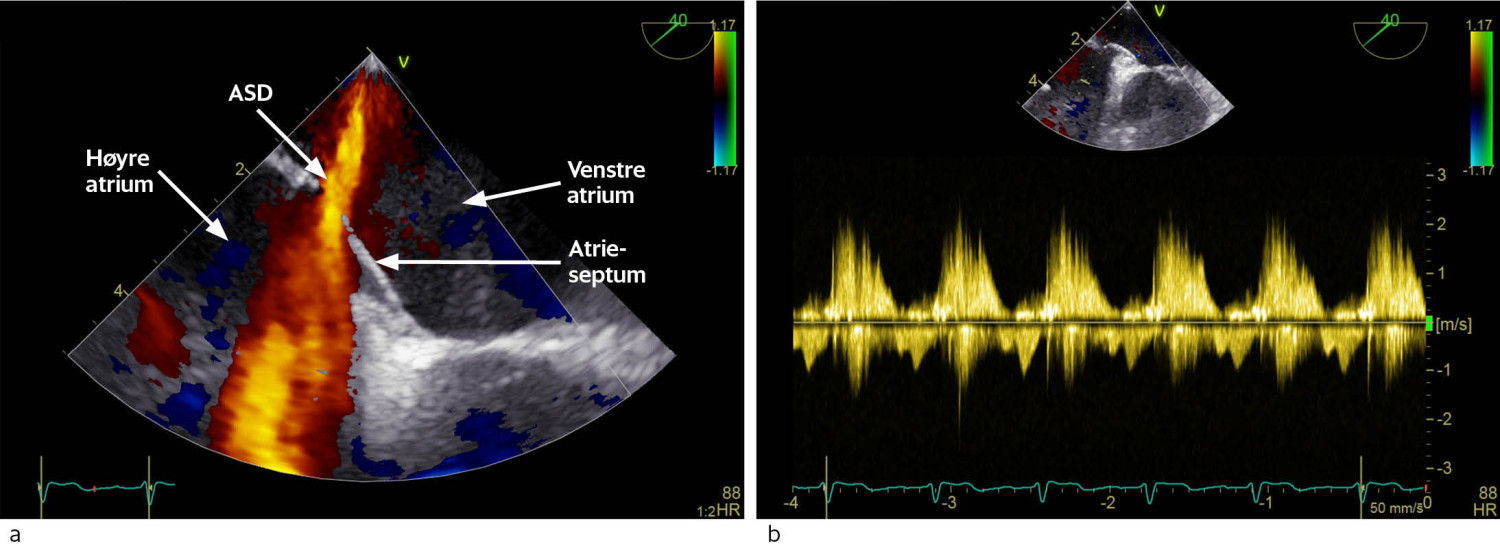

Pasienten kom til hjertemedisinsk utredning ved universitetssykehuset et par måneder senere. Transtorakal og transøsofageal ekkokardiografi bekreftet omfattende trikuspidalpatologi med chordarupturer og prolaps av anteriore segl (figur 1a). Trikuspidalannulus var dilatert, og det var manglende systolisk kontakt mellom klaffeseglene. Dette forårsaket en stor lekkasje (Figur 1b) med systolisk reversering av blodstrøm i levervenene. Vena cava inferior var dilatert og hadde manglende respirasjonsvariasjon, forenlig med høyt høyresidig fylningstrykk. Høyre ventrikkel var dilatert, med normal veggtykkelse og god langaksebevegelse. Høyre atrium var også dilatert. I tillegg hadde pasienten en forholdsvis stor medfødt atrieseptumdefekt i sekundumområdet av atrieseptum (figur 2a og b). Det var ikke ekkokardiografiske holdepunkter for pulmonal hypertensjon.

Atrieseptumdefekter er blant de vanligste medfødte hjertefeilene og forekommer hos ca. 0,5–2 per 1 000 fødte (4). Defektene deles i tre hovedgrupper: sekundumdefekter, primumdefekter og sinus venosus-defekter. Sekundumdefekter er vanligst og skyldes vedvarende fysiologisk atrieforbindelse fra fosterlivet. Konsekvensene av atrieseptumdefekt avhenger hovedsakelig av størrelsen på defekten. Større defekter gir vanligvis symptomer i løpet av livet (4). Grunnet trykkforholdene i hjertet vil blodstrømmen hovedsakelig ha retning fra venstre til høyre atrium (venstre-høyre-shunt). Dette kan forårsake volumbelastning av høyre hjertehalvdel og økt blodstrøm i lungekretsløpet. Vedvarende volumoverbelastning og dilatasjon av høyre hjertehalvdel kan forårsake supraventrikulære arytmier. Høyresidig hjertesvikt og økt blodvolum i lungekretsløpet kan gi symptomer som fatigue, redusert funksjonskapasitet og hyppige pneumonier. I ytterste konsekvens kan det gi leverstuvning med leversvikt, ascites og perifere ødemer. Ekkokardiografi står sentralt i diagnostikken av atrieseptumdefekter. Tegn på signifikant venstre-høyre-shunt er blant annet dilatasjon av høyre atrium, diastolisk avflating eller paradoks bevegelse av ventrikkelseptum og dilatasjon av v. cava inferior (5).

Den kardiologiske utredningen ved universitetssykehuset inkluderte koronar angiografi, som viste signifikant stenose på circumflexarterien. Høyresidig hjertekateterisering bekreftet generelt redusert oksygensaturasjon. Ved kateterføring via atrieseptumdefekten var det også tilgang til venstre atrium og lungevener. Lungevenene hadde normal oksygensaturasjon, men det var betydelig saturasjonsfall fra lungevener til venstre atrium. Dette kan forklares med tilførsel av blod med lav oksygenering fra høyre til venstre atrium via en stor atrieseptumdefekt. Det var ikke pulmonal hypertensjon eller høy lungekarmotstand. Spirometri viste normale funn, med forsert vitalkapasitet (FVC) på 4,2 l og forsert ekspiratorisk volum etter ett sekund (FEV1) på 77 %.